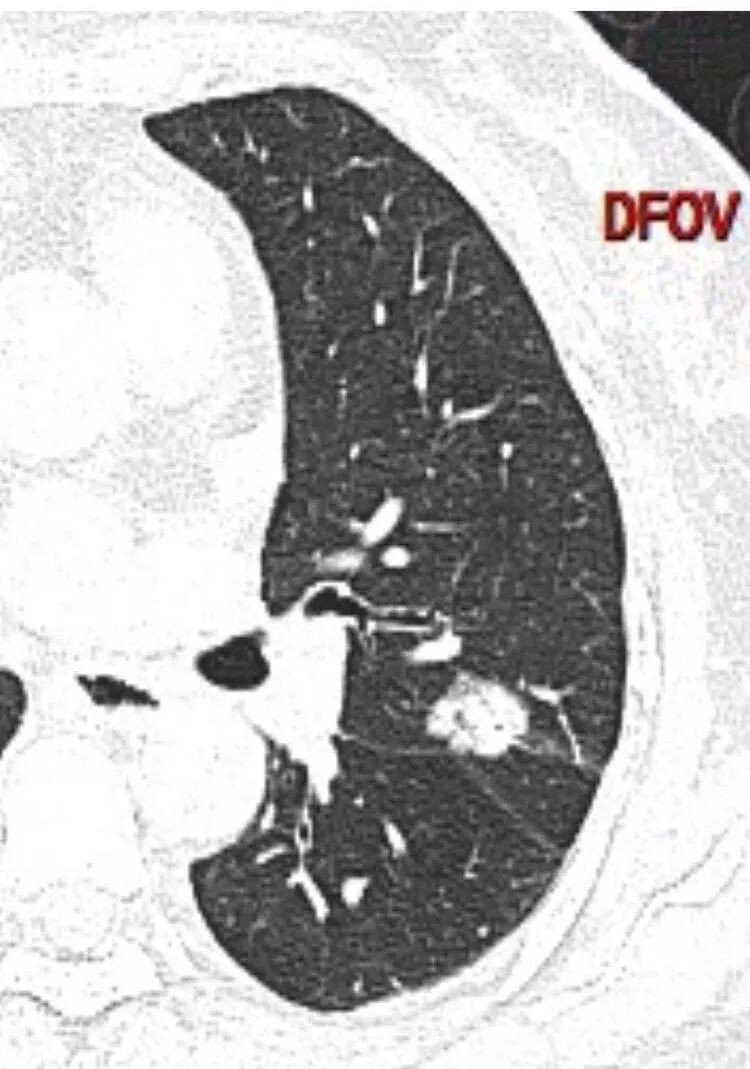

马宁强:考虑肉芽肿性病变,隐球菌可能彭君:左肺上叶舌段混合毛玻璃密度结节 边缘清 有分叶毛刺 斜裂胸膜凹陷征 考虑腺癌可能王秀仙:左肺上叶结节,部分边缘磨玻璃清晰,有分叶毛刺,支气管通过并扩张,其外侧小叶间隔不规则增厚,胸膜牵拉,考虑腺癌。鉴别慢性炎症。田园晚风:左肺上叶多个小结节融合呈分叶状,可见叶间裂牵拉,考虑腺癌张帅:左肺上叶后段结节,内可见支气管穿过,病灶周围有少许毛刺,病灶边缘有浅分叶,对叶间胸膜有牵拉,部分位置呈对叶间胸膜推移。考虑为恶性病变,腺癌?。杨泽锋:混合型磨玻璃结节,边缘有膨隆、有凹陷,明显的胸膜牵拉,考虑腺癌可能大;内部支气管通畅、似乎有鬼脸征,所以鉴别隐球菌Lotus:病灶内部有结节感,这个大小似乎是次级肺小叶的大小,考虑炎性,有冠位最好了。但是胸膜牵拉有些恶性提示心包右侧软组织密度影考虑心包隐窝Yiren Sishui(厶水伊人):叶间裂有膨隆有凹陷,考虑恶性,腺癌可能

徐婕:同意恶性腺癌可能岁月:女,56;空泡,分叶毛刺,牵拉线,胸膜凹陷征,有强化,浸润性腺癌。THINKER:左舌见结节,膨胀为主,部分收缩,分叶丶短丶硬毛刺,牵拉斜裂,有小空泡,支气管穿行,有强化,常规腺癌丽:左肺上叶近胸膜下结节,胸膜牵拉,边缘膨隆,并可见深分叶及毛刺,内有空泡,增强后可见强化,倾向腺癌淘时光:混合磨玻璃结节,实性部分较多,内见支气管穿行,腺癌首先考虑了…☀:左肺上叶结节影,实性,边缘分叶征,其内可见空泡,部分膨胀生长,局部叶间裂牵拉上移,叶间裂光滑增厚,首先考虑肿瘤黄棘:左肺上叶结节,边缘彭隆, 周围磨玻璃影边界清,内部可见扩张支气管,叶间胸膜牵拉,考虑腺癌心灵鸡汤:左肺上叶舌段近斜裂处混合性结节,以实性成分为主,有分叶、毛刺,牵拉邻近叶间、脏层胸膜,增强有强化,影像学上看偏恶性,分类LU-RADS 4C类,MIA浸润性腺癌可能,鉴别肉芽肿性病变、隐球菌,请老师指点!THINKER:这个如果是腺癌,应该是IAC了,过MIA了,个人看法,罗老师一切∮随缘:左肺叶裂胸膜下结节,边缘收缩弱,周围有GGO,边界清楚,形态欠规则,其内似有支气管穿行,增强扫描轻度均匀强化,考虑1肉芽肿性病变(隐球,炎性假瘤)2:浸润性腺癌Clover:考虑腺癌,实性为主混合有少许边界清晰ggo,边缘膨隆,其内支气管气象不规则,有收缩力。Coke with ice:还有一个疑问请教一下:这个是混合磨玻璃结节还是实性结节?个人倾向于后者。心灵鸡汤:有部分磨玻璃Coke with ice:实性结节周围GGO初学者:实性,周围有毛玻璃晨:有浅分叶,有毛刺,有叶间裂牵拉,内有囊泡,考虑腺癌。初学者:稍等,我等会开电脑看,但是感觉和你们一样,感觉是一个典型病例来着Coke with ice:这个人我也倾向于腺癌。但是诊断腺癌还有一个比较疑惑的地方,肺窗病变密度显示比较实,但是纵隔窗病灶范围明显比肺窗小,腺癌可以解释的通吗?张小兵:混合磨玻璃结节,内见支气管穿行,分叶,胸膜牵拉从凹陷处进入,腺癌首先考虑小微:

脐凹、分叶

Coke with ice:@南边 老师这里是不是脐凹征这个好像和胸膜相连,不是标准的脐凹征南边:定义上是指血管、支气管从凹陷处进入远端是出去进入、出去是两个概念

近肺门侧是进入,意味着血管支气管顶住,导致局部的肿瘤生长受限;出去是指血管穿过肿瘤从远端延伸出去所以我认为有价值,但不是脐凹征。